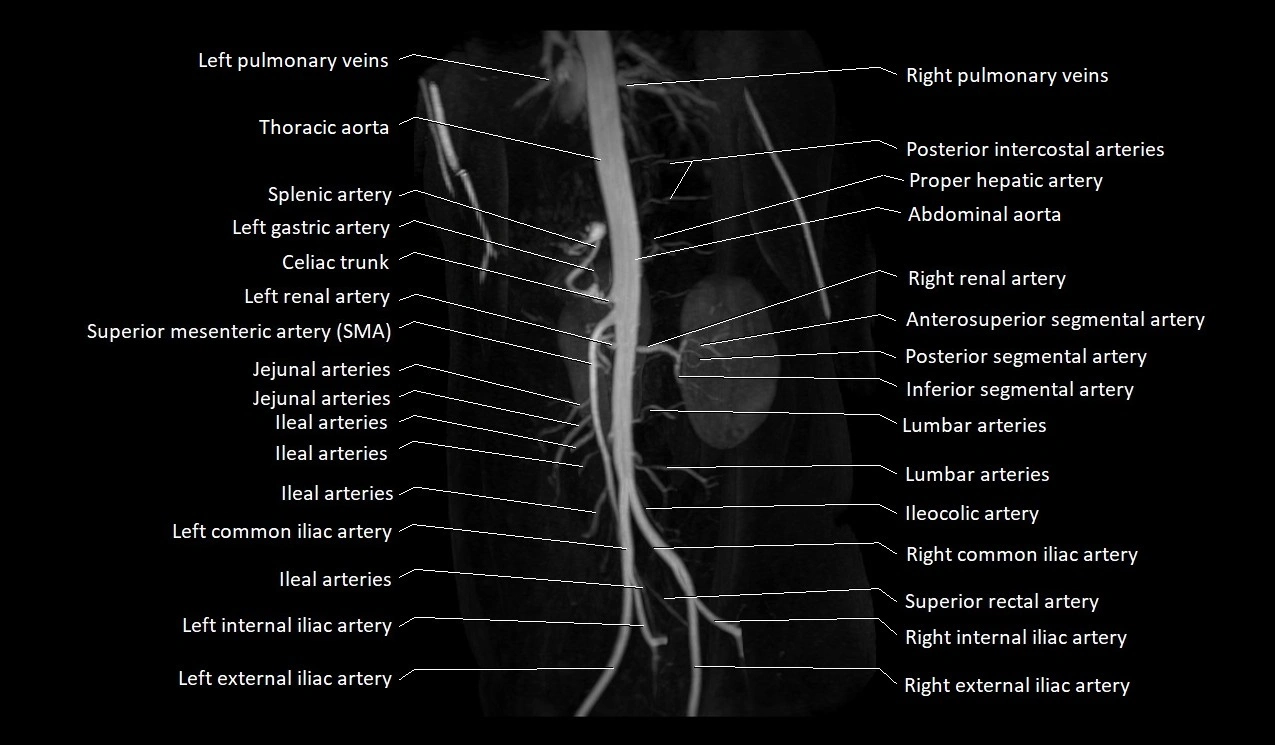

CT images

image